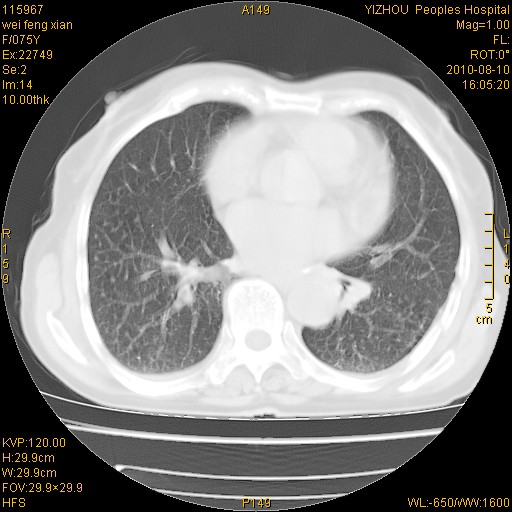

标题: CT28313:两肺弥漫性病变 [打印本页]

标题: CT28313:两肺弥漫性病变

女,75岁,患者反复头昏乏力面色苍白3年,再发10天入院。临床贫血查因。

双肺间质增生并右肺上叶炎性改变,不除外右肺上叶结核病肺内播散

考虑右肺上叶炎症合并双肺结核可能性大,建议上传纵隔窗ct图片。

双肺结核可能性大

考虑尘肺并结核;右上肺支气管扩张!

结核、尘肺、支气管肺泡癌都不能除外

右肺上叶继发性肺结核伴肺内血型播散!

考虑右肺上叶继发性肺结核伴两肺播散。